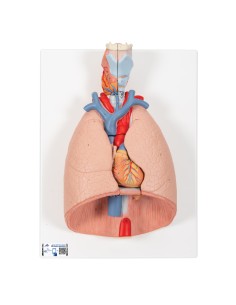

Du crâne en 22 parties à verrouillage magnétique aux modèles de colonne vertébrale, des modèles d'articulation aux modèles de cœur, chaque pièce de notre collection est conçue pour une immersion totale dans l'étude de l'anatomie humaine. Nos modèles, réalisés à partir de scans d'os réels, garantissent une expérience tactile authentique et une fidélité de poids presque identique aux originaux.

Indispensables aux étudiants comme aux professionnels, nos modèles anatomiques sont des outils pédagogiques qui permettent d'observer les structures anatomiques avec précision, en évitant les dissections ou les études invasives. Ils sont également utiles pour expliquer les pathologies aux patients, ce qui rend la communication plus efficace et permet de gagner un temps précieux.